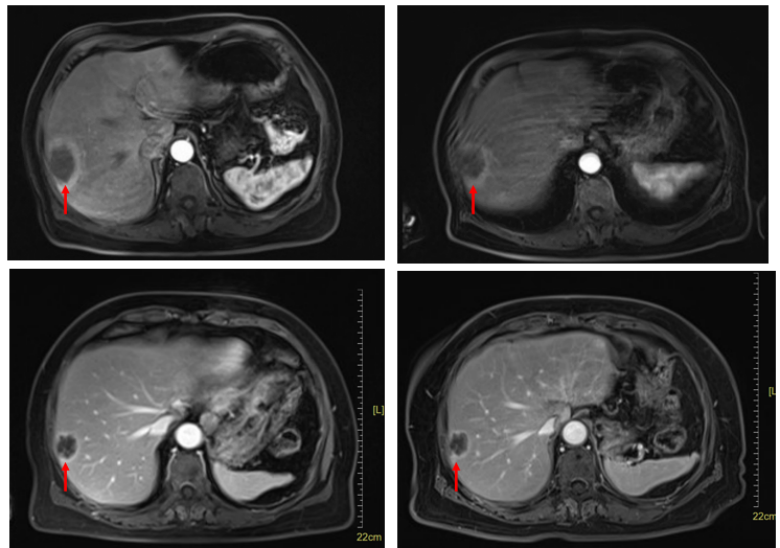

患者于2024年6月17至11月12日予以“TAS-02+贝伐珠单抗”方案治疗10周期。

定期复查腹部CT,提示肝内病灶较前明显缩小(图3)。疗效评估为PR。